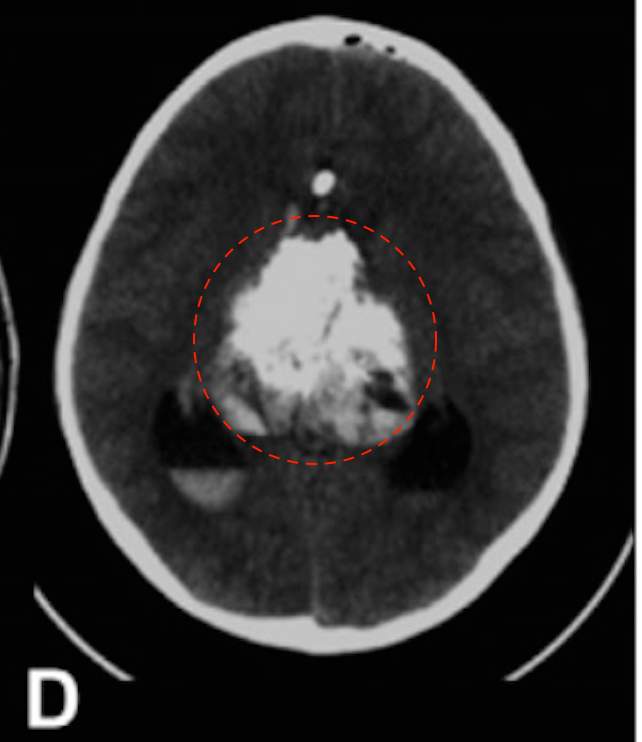

12岁男孩,因出现近3周的头痛和急性恶化而入院治疗。

(D)尝试左额半球间经胼胝体切除术后的CT扫描显示脑室内和腔内内出血。